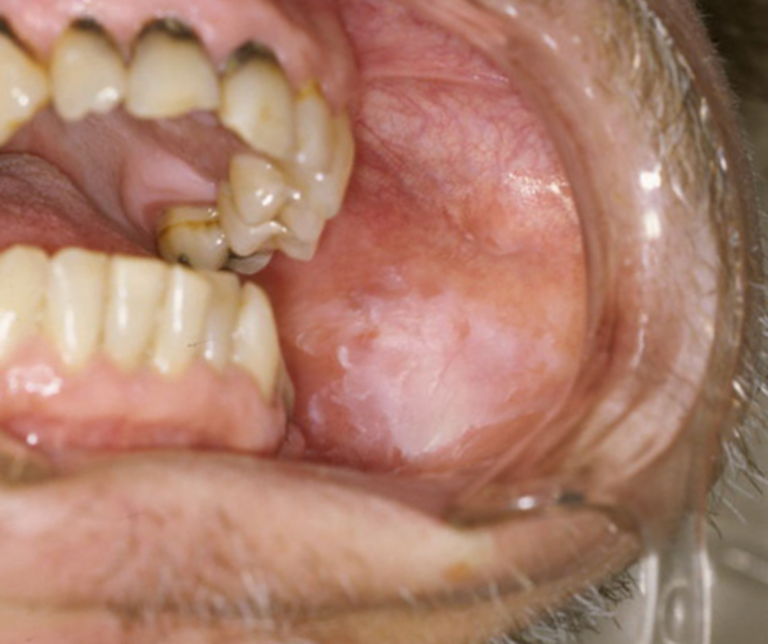

白板症(はくばんしょう)【前癌病変】

粘膜の一部が白くなり、こすっても取れない状態です。

痛みがないことが多いですが、実はこれは「ガンの手前の状態(前癌病変)」である可能性があります。

口腔外科の経験を持つ医師による、慎重な経過観察や精密検査が必要なケースです。